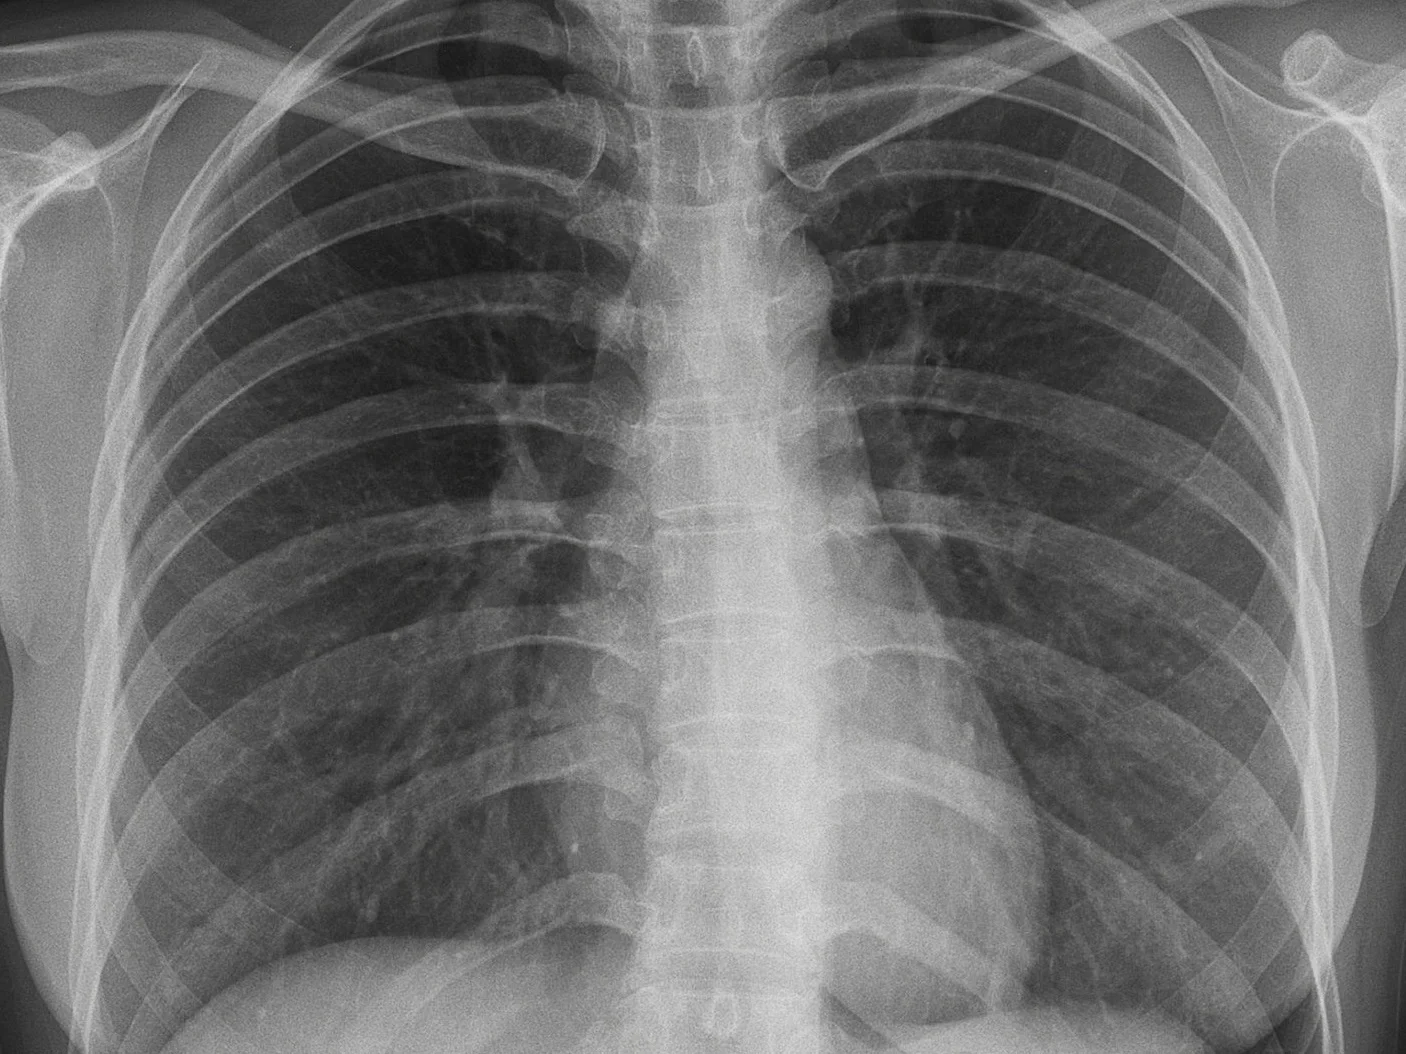

Enhancing the public health impact of latent tuberculosis infection diagnosis and treatment: A pragmatic cluster randomised trial

PRIMARY OBJECTIVE: To estimate the increase in number of close contacts (of pulmonary tuberculosis patients) who are identified, investigated, initiated, and completed latent tuberculosis infection (LTBI) therapy. The intervention is a standardised public health evaluation (Cascade analysis), with use of operational modeling analysis to select effective interventions from a "public health toolkit".